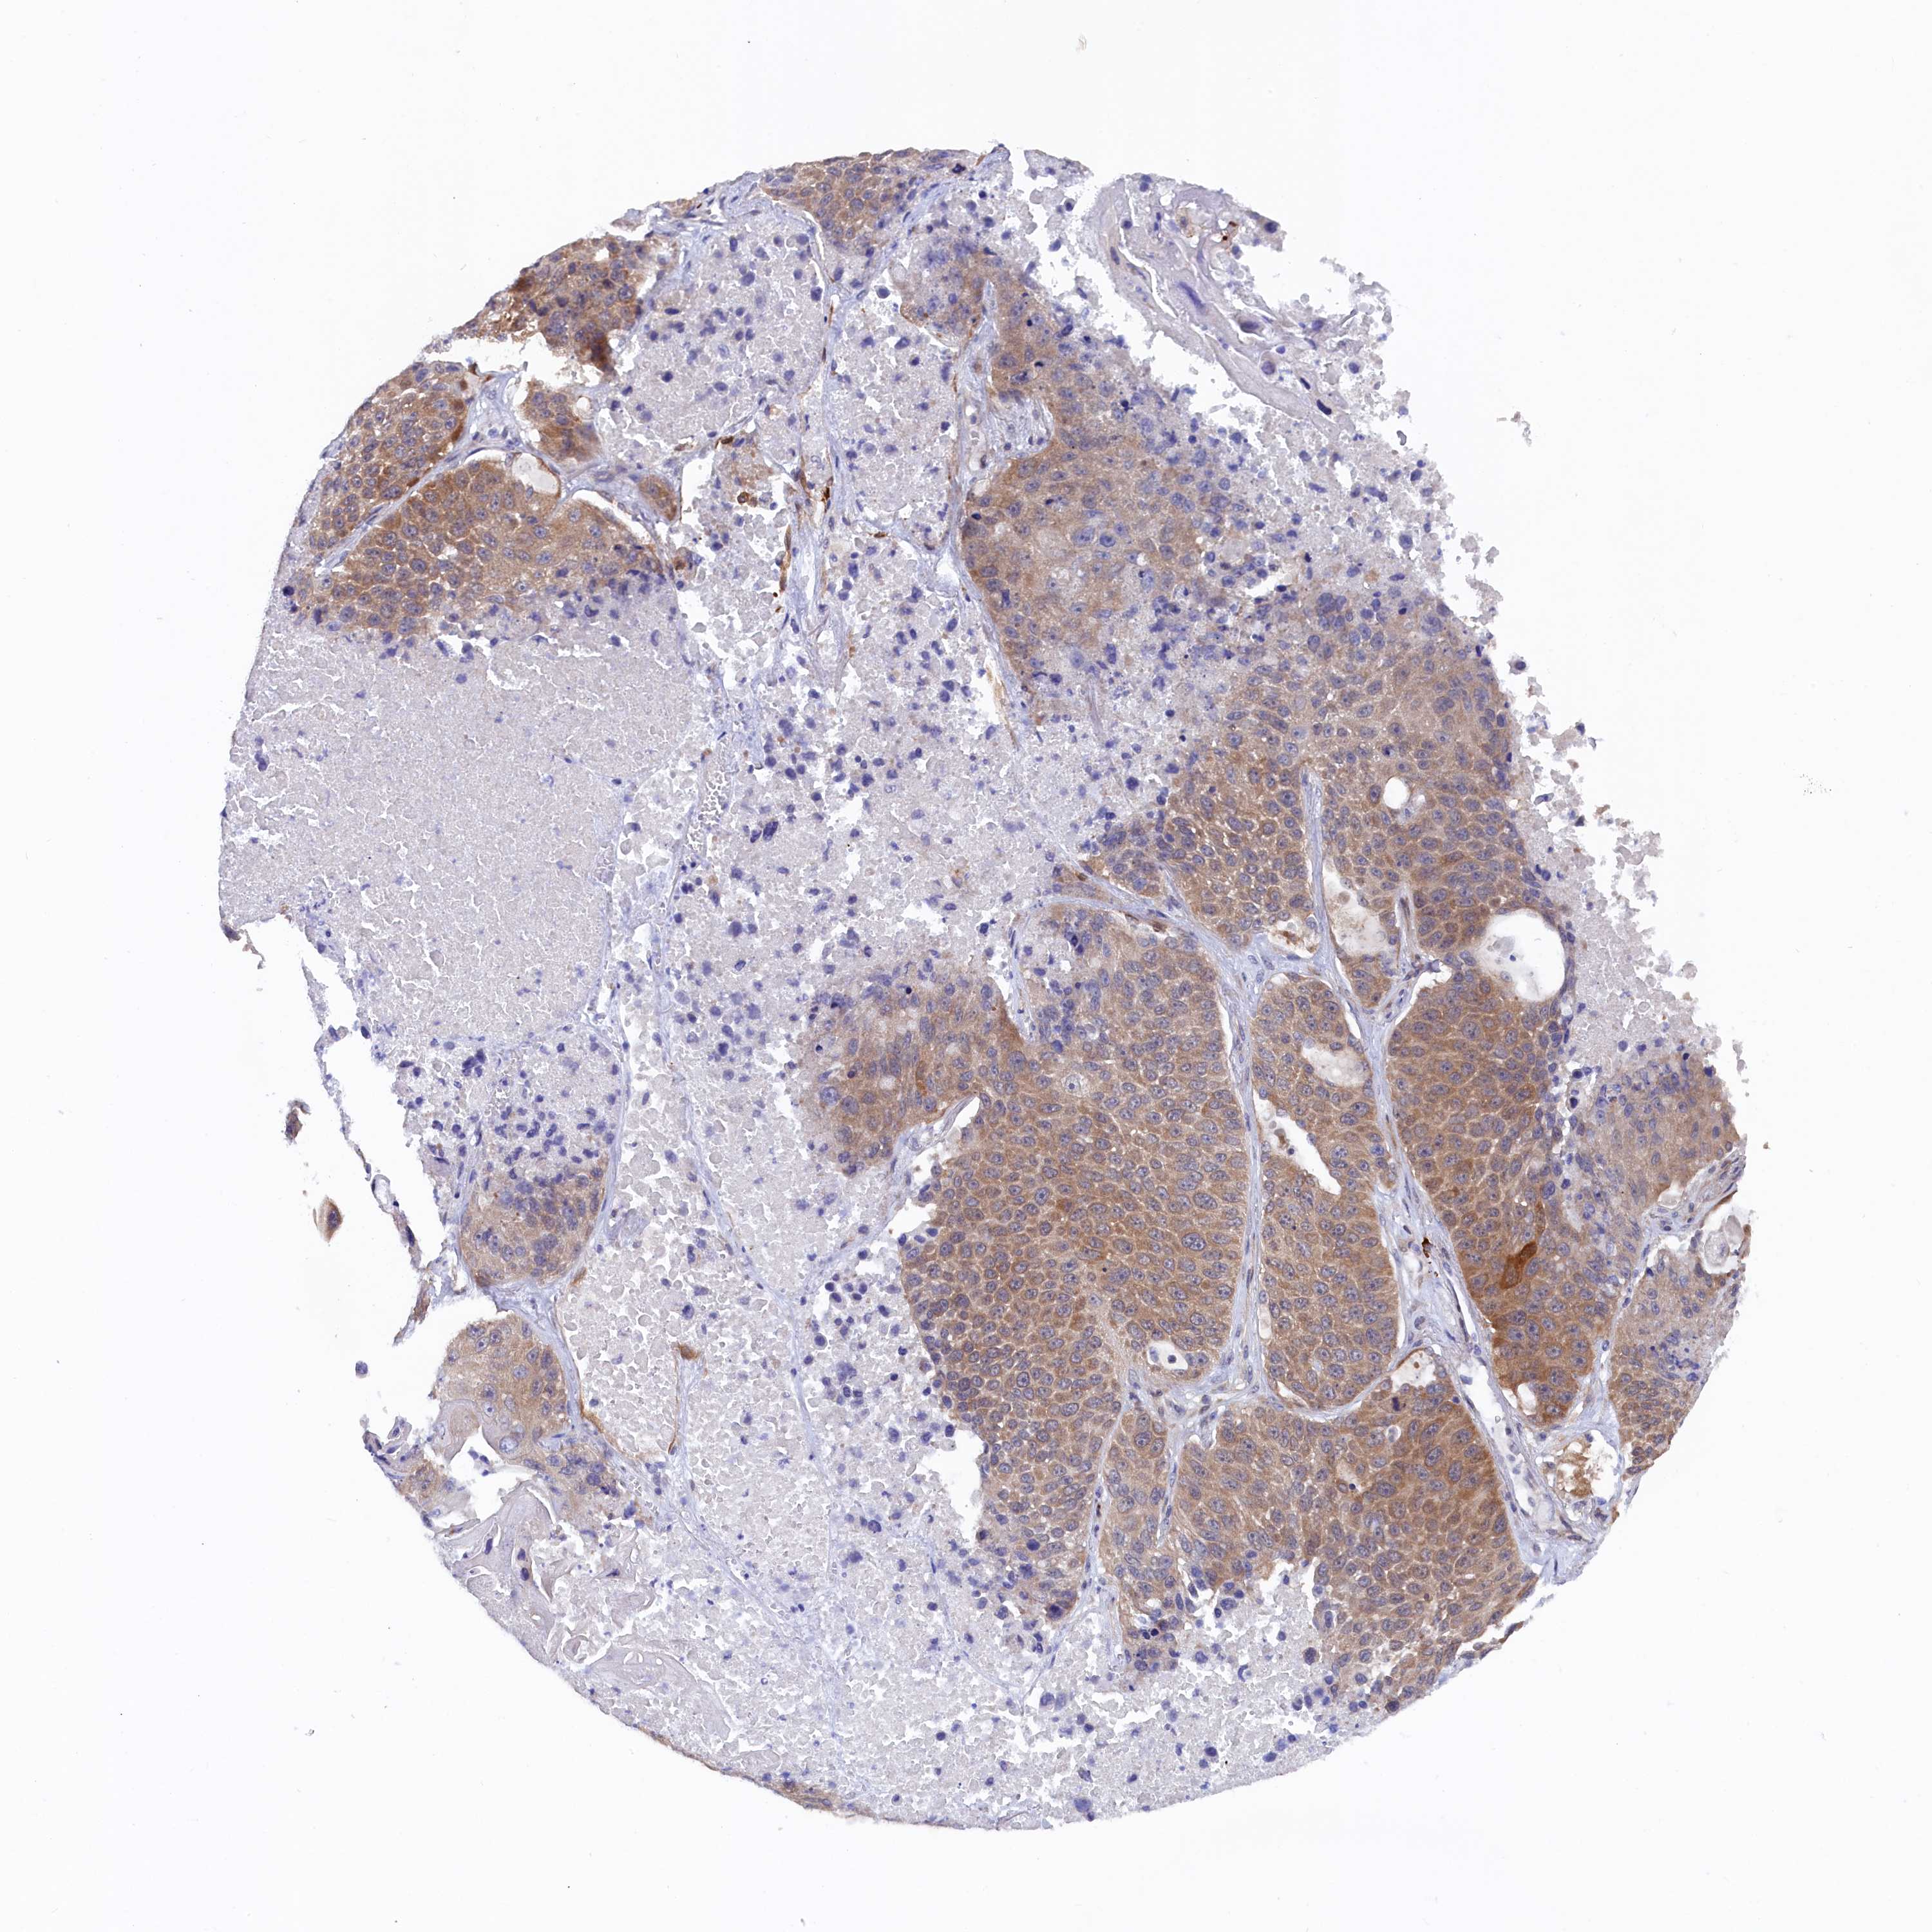

LUNG SQUAMOUS CELL CARCINOMA (TCGA) - Interactive survival scatter ploti

The Survival Scatter plot shows the clinical status (i.e. dead or alive) for all individuals in the patient cohort, based on the same data that underlies the corresponding Kaplan-Meier plots. Patients that are alive at last time for follow-up are shown in blue and patients who have died during the study are shown in red.

The x-axis shows the expression levels (FPKM) of the investigated gene in the tumor tissue at the time of diagnosis. The y-axis shows the follow-up time after diagnosis (years). Both axes are complimented with kernel density curves demonstrating the data density over the axes. The top density plot shows the expression levels (FPKM) distribution among dead (red) and alive patients (blue). The right density plot shows the data density of the survived years of dead patients with high and low expression levels respectively, stratified using the cutoff indicated by the vertical dashed line through the Survival Scatter plot. This cutoff is automatically defined based on the FPKM cutoff that minimizes the p-score. The cutoff can be changed by dragging the vertical line or by entering a cutoff value in the square labeled "Current cut-off".

Under the Survival Scatter plot the p-score landscape (black curve; left axis) is shown together with dead median separation (red curve; right axis). Dead median separation is the difference in median mRNA expression between patients who have died with high and low expression, respectively. It is calculated as follows: median FPKM expression of dead patients with high expression - median FPKM expression of dead patients with low expression. This is intended to aid the user in visually exploring custom cutoffs and the associated p-scores and dead median separation.

Individual patient data is displayed and can be filtered by clicking on one or more of the category buttons on the top of the page. Categories describing expression level and patient information include: high, low, alive, dead, female, male and tumor stages. The scale of the x-axis can be toggled between linear and log-scale by clicking on the "x log" button. Mouse-over function shows TCGA ID, patient information and mRNA expression (FPKM) for each patient.

& Survival analysisi

Kaplan-Meier plots summarize results from analysis of correlation between mRNA expression level and patient survival. Patients were divided based on level of expression into one of the two groups "low" (under cut off) or "high" (over cut off). X-axis shows time for survival (years) and y-axis shows the probability of survival, where 1.0 corresponds to 100 percent.

JPT2 is not prognostic in Lung Squamous Cell Carcinoma (TCGA)

Best expression cut offi

Based on the FPKM value of each gene, patients were classified into two groups and association between prognosis (survival) and gene expression (FPKM) was examined. The best expression cut-off refers the FPKM value that yields maximal difference with regard to survival between the two groups at the lowest log-rank P-value. Best expression cut-off was selected based on survival analysis .

When clicking on this number, the vertical dashed line indicating cut-off, the interactive survival plot, and the Kaplan-Meier curve will be adjusted to show results based on the best expression cut-off.

: 60.41

P scorei

Log-rank P value for Kaplan-Meier plot showing results from analysis of correlation between mRNA expression level and patient survival.

N/A

Average pTPM 74.8

Number of samples 489